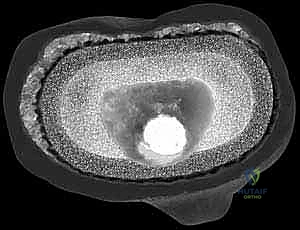

يعتمد الدكتور هطيف على أحدث تقنيات التصوير الطبي، بما في ذلك الأشعة السينية الرقمية (Digital X-rays) في وضعيات الوقوف، والتصوير المقطعي المحوسب (CT Scan) ثلاثي الأبعاد لتقييم حجم العظم المتبقي بدقة متناهية. كما يتم إجراء فحوصات دم شاملة وسحب سائل من الركبة (Aspiration) لاستبعاد وجود أي عدوى بكتيرية خفية.

بعد إزالة المفصل، يتم تنظيف العظم بالكامل من أي أنسجة ملتهبة أو أسمنت متبقي. هنا، تتجلى الرؤية الحقيقية لحجم العيب العظمي (AORI Type II أو III). يتم قياس الفجوات العظمية بدقة باستخدام قوالب تجريبية.

4. تحضير الساق وتركيب الدعامات المعدنية (Tibial Preparation and Augmentation)

لتعويض العظم المفقود وإعادة مستوى المفصل (Joint Line) إلى ارتفاعه التشريحي الطبيعي، يقرر الدكتور هطيف نوع الدعامة المعدنية المناسبة:

* إذا كان العيب سطحياً وفي جهة واحدة، تُستخدم الكتل أو الأوتاد المعدنية (Wedges/Blocks) التي تُثبت بأسفل الغرسة الجديدة.

* إذا كان العيب كبيراً وعميقاً في المركز، تُستخدم المخاريط أو الأكمام المسامية (Cones/Sleeves). يتم حفر العظم التالف بشكل هندسي دقيق ليحتضن هذا المخروط المعدني الذي يوفر أساساً صخرياً متيناً.